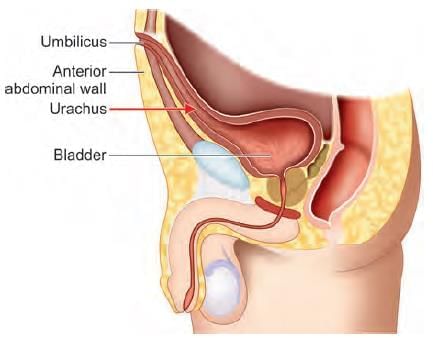

Adult derivative of the arrow marked structure in the following diagram is: (NEET-PG 2023)

Which of the following ligament develop in the arrow marked structure? (NEET-PG 2022)